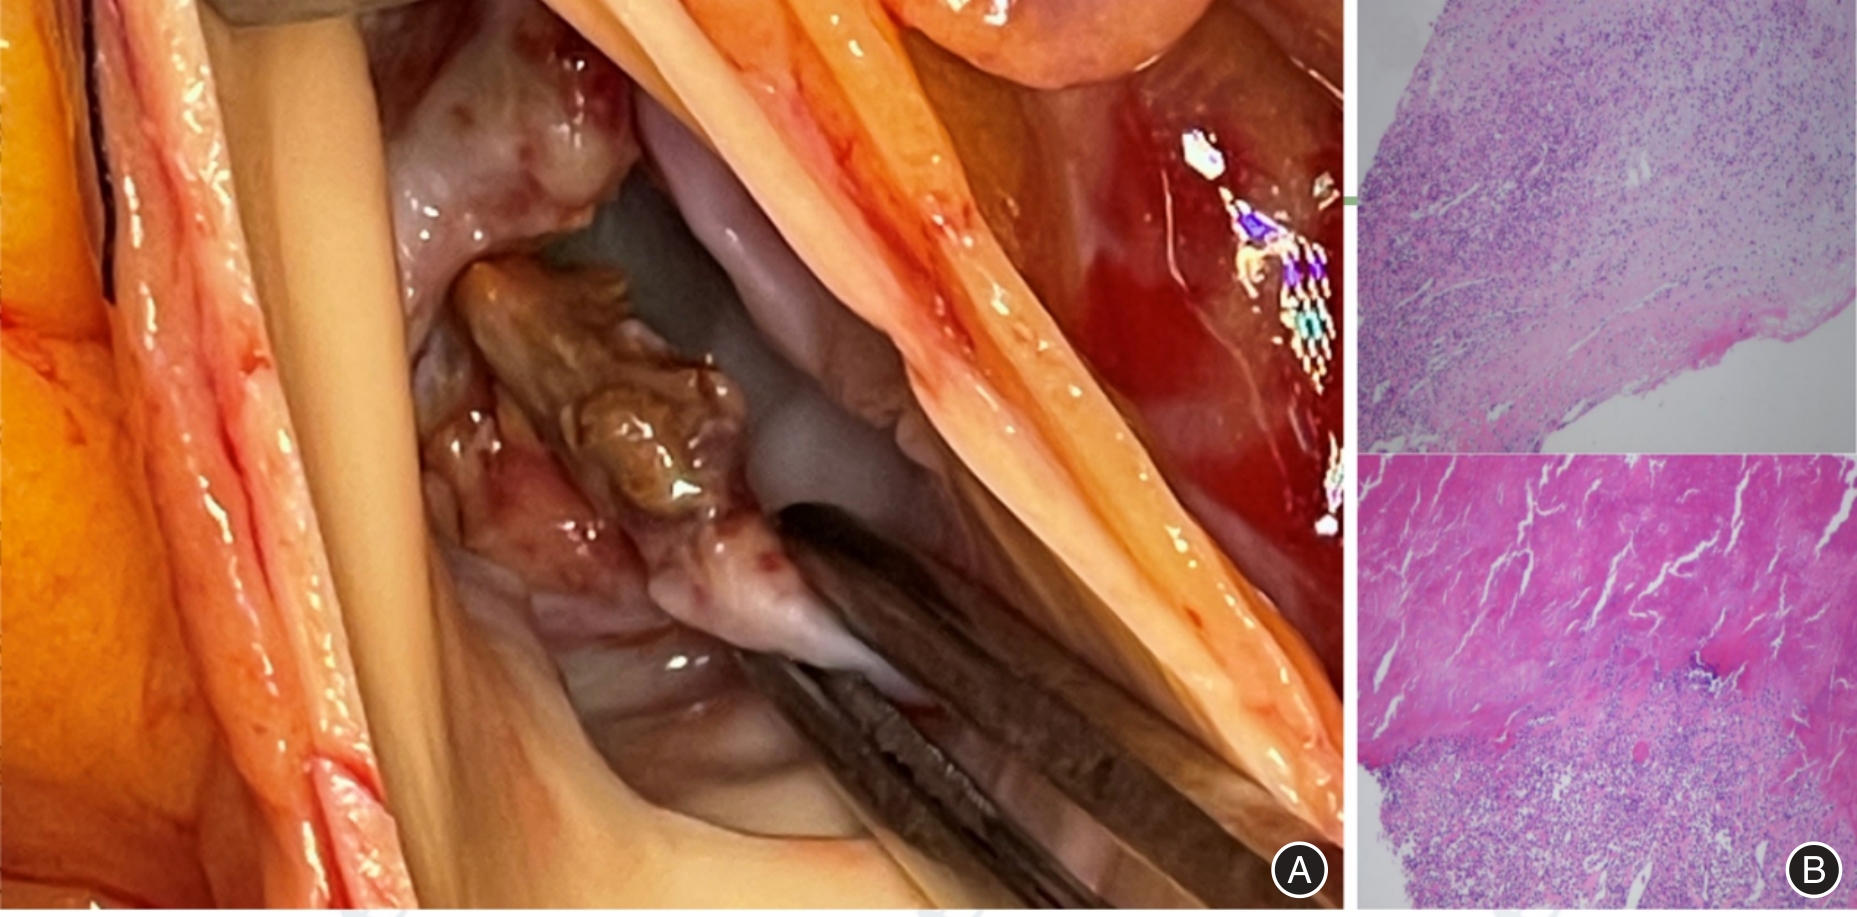

1例36岁青年男性因胸闷、气促10余天入院,超声心动图提示主动脉瓣重度关闭不全、主动脉瓣赘生物、二尖瓣重度关闭不全、左房左室增大。经多学科会诊讨论,以患者主动脉瓣赘生物为切入点,将患者瓣膜病病因聚焦在血培养阴性的感染性心内膜炎(IE)和非细菌性血栓性心内膜炎,并与风湿性心脏瓣膜病相鉴别。最终经外科主动脉瓣置换术取赘生物行组织病理学、生物培养及病原微生物高通量宏基因组二代测序,最终确诊为贝纳特柯克斯体导致的主动脉瓣感染性心内膜炎(Q热IE)。

A 36-year-old male patient was hospitalized due to persistent chest tightness and dyspnea lasting over 10 days. An echocardiogram revealed significant aortic valve regurgitation, the presence of vegetation on the aortic valve, severe mitral valve regurgitation, and enlargement of both the left atrium and left ventricle. Following a comprehensive multidisciplinary consultation, the focus was directed towards the aortic valve vegetation as the primary concern, with particular attention given to the potential diagnosis of blood culture-negative infective endocarditis (IE) and non-bacterial thrombotic endocarditis, while differentiating it from rheumatic heart disease. Ultimately, the vegetation was excised during a surgical aortic valve replacement procedure, which facilitated histopathological examination, biological culture, and high-throughput metagenomic sequencing of pathogenic microorganisms. The definitive diagnosis was established as aortic valve infective endocarditis (Q fever IE) leading by infection of Coxiella burnetii.